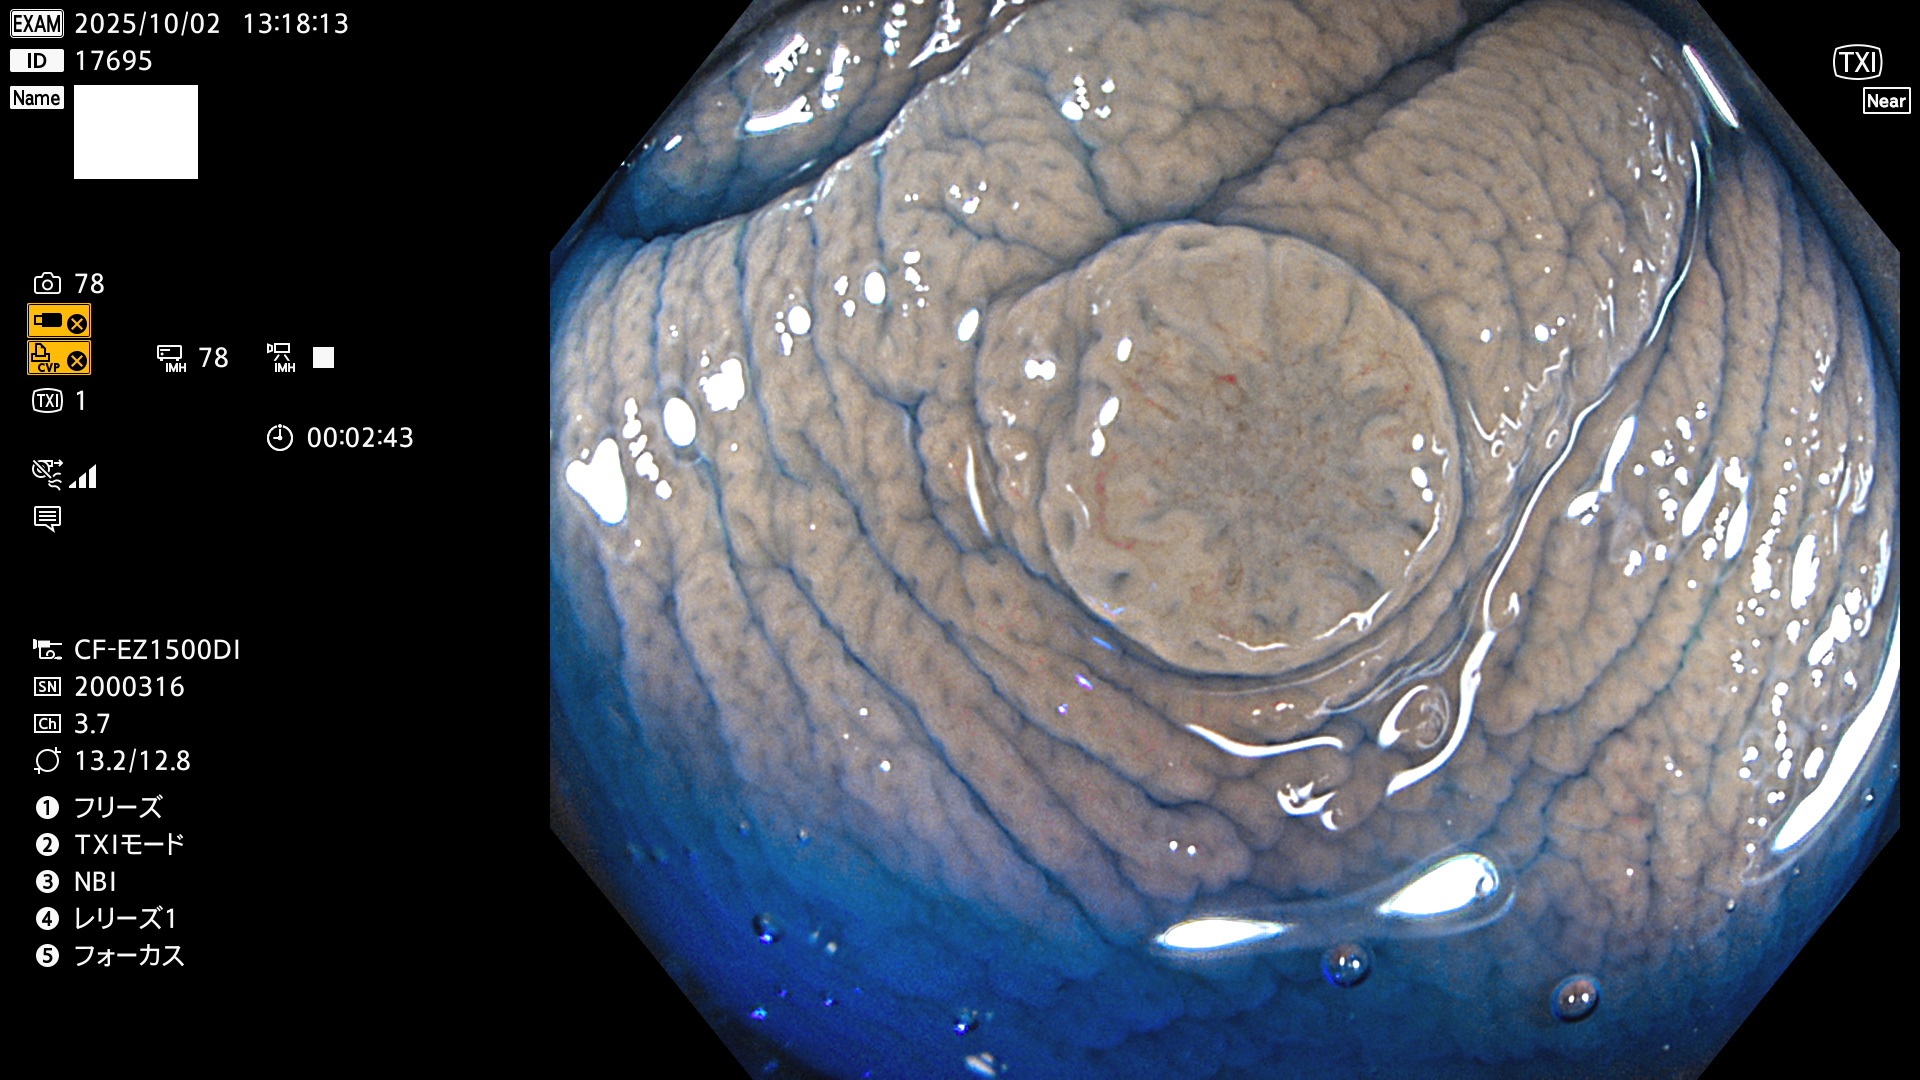

完全に平坦な物をUb、陥凹している物をUcと呼びます。Ubは認識が困難で、Ucはびらん(炎症)と紛らわしいために見落とされやすく、「内視鏡後・大腸癌」の原因になります。

専門的)Uc=De Novo癌? 内視鏡の解像度が低かった時代、このような説もありました。しかし今日の高精度内視鏡では良性の微小なUc型腺腫(APC遺伝子異常の腺腫)が日常的に見つかります。Ucこそが多段階発癌(Adenoma-Carcinoma Sequence)のMain Routeです。

毎週の検査(木・金・土・日)に発見されたUbとUc型・腺腫を、その週の日曜の夜にUPし1週間、提示します。

写真公開の目的は「透明性・信憑性の担保」ですが、公開を希望されない方はメールで御連絡下さい。直ちに削除いたします。

2025年10月2日〜10月5日の4日間(40件)で9個 (Uc_ADR=9個/40人=23%)